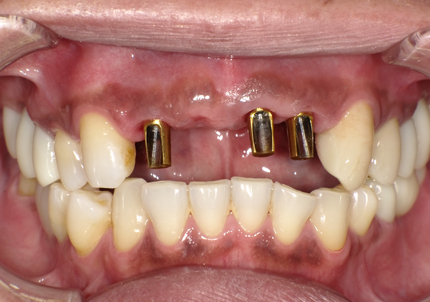

19.アバットメント装着(2020年1月)

ISQ値 右上2 (71) 左上1 (73) 左上2 (72)

24.口腔内写真